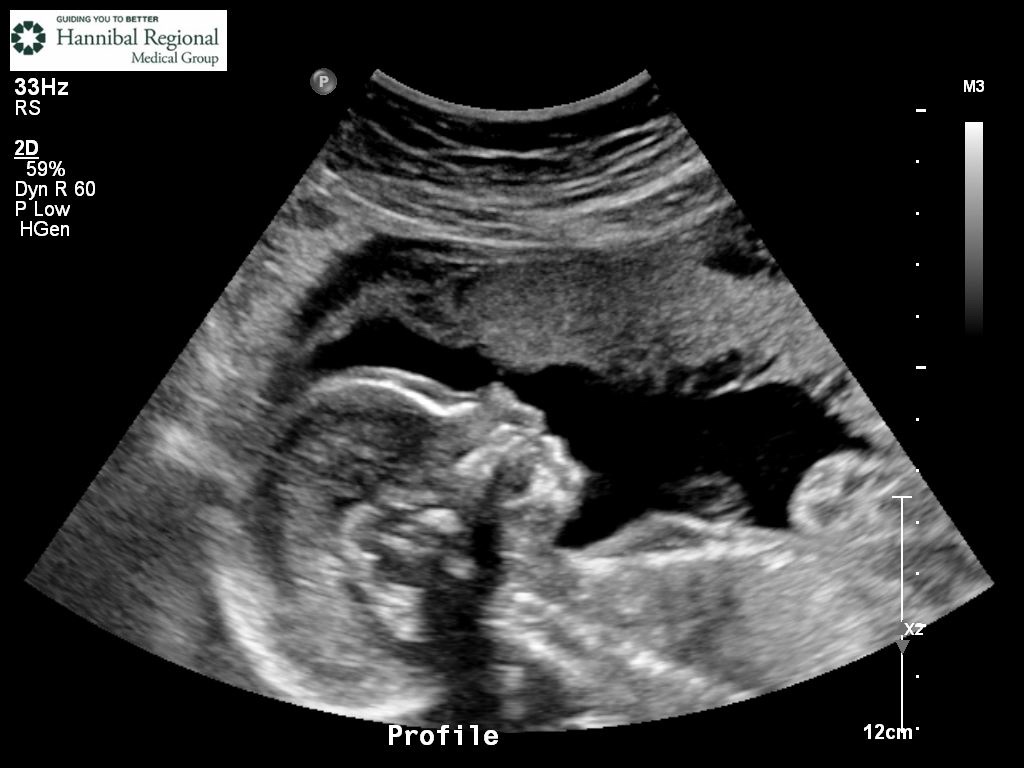

We had our 20 week appointment and discovered that we’re having a baby BOY! π We’re naming him Oliver Alan Neice, Ollie for short. π They saw no issues, and he is growing normally. Thank you, Jesus! My belly is starting to grow at a fast rate, but I’ve only gained back 4 lbs. I have so much more energy but still get winded easily. I can finally eat again! Wahoo!! But I’ve noticed some foods do not settle the same anymore. π€’ I may never eat Taco Bell again. Physically, I am doing pretty good. I ache, of course. And this growing belly making things slightly awkward and uncomfortable. I’m sure that only gets worse!

We had a slight scare when the doctors office called to tell me they needed to repeat the 20 week ultrasound at 28 weeks. The lady didn’t know much info. She only said something about his hands and feet. Sitting on that stressful thought for awhile was not very fun, but I put all faith in God. We figured, hands and feet? We can handle that. I had an appointment (24 weeks) and the doctor assured me that they just didn’t get good enough pictures. They are not suspecting or curious about any issues. Again, thank you, Jesus! I can now relax until my next appointment at 28 weeks when I get to see baby Ollie again! I also will do the glucose test, and receive RhoGam shot. This means I’ll get pricked with a needle twice. Not looking forward to it. π₯΄